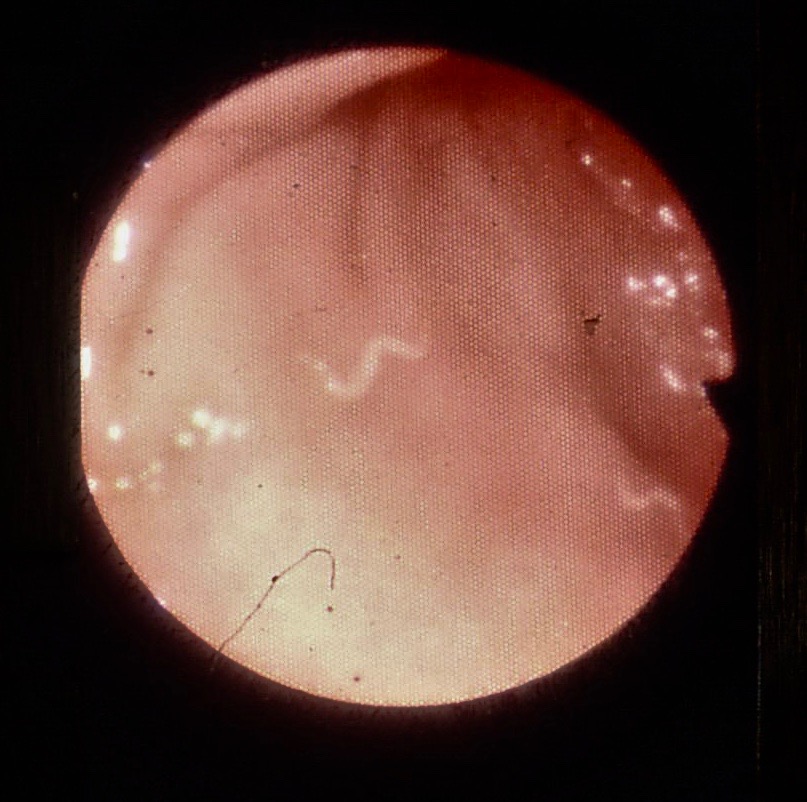

Fishing eye syndrome. Eye Worm YouTube White Threads In Eyes They may look like spots,. Have you noticed flashes or threads of light in the corners of your eye and wondered what’s going on? Symptoms that should be seen by a doctor include light flashes in one or both eyes, a dark shadow or. Floaters are tiny clumps of gel or cells inside the vitreous that. Flashes in your eye. White Threads In Eyes.